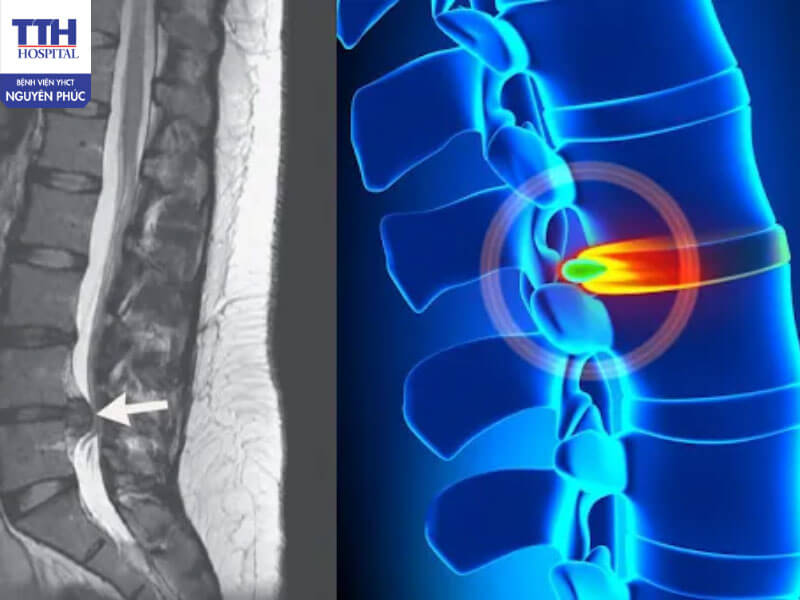

Đĩa đệm là phần nằm giữa các đốt sống, có cấu trúc mềm, đàn hồi giúp cột sống vận động linh hoạt và giảm xóc khi cơ thể cử động. Khi phần nhân nhầy bên trong đĩa đệm thoát ra ngoài qua chỗ rách hoặc nứt của bao xơ, nó sẽ chèn ép lên rễ thần kinh hoặc tủy sống, gây ra các triệu chứng đau nhức, tê mỏi, thậm chí yếu liệt chi.

Thoát vị đĩa đệm thường gặp nhất ở hai vị trí:

• Cột sống thắt lưng: chiếm hơn 70% các trường hợp, gây đau lưng lan xuống chân (đau thần kinh tọa).

• Cột sống cổ: gây đau vùng cổ, vai gáy, tê lan xuống cánh tay.